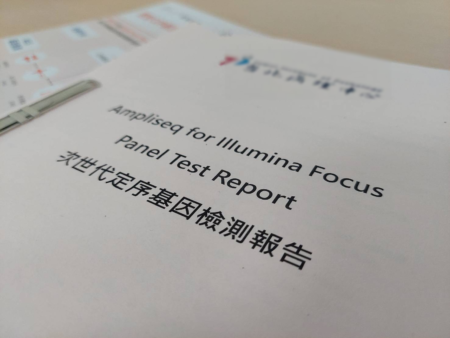

【大紀元2025年04月30日訊】(大紀元記者陳文敏台灣苗栗報導)62歲的陳女士因慢性咳嗽及背痛到醫院就醫,診斷為第四期肺腺癌,由於她的常見致癌突變基因檢測為陰性,無法使用目前臨床效果最好的EGFR標靶藥物治療,液態切片次世代基因檢測也未能找到相關突變基因及有效的藥物治療,加上使用第一線及第二線的化學治療皆出現抗藥性及副作用。因此,在醫療團隊的建議下,接受微創手術取腫瘤組織做次世代定序基因檢測,終於找到罕見的Met突變基因的標靶藥物治療,讓病人有重生的希望,同時透過健保給付,幫助病人及家屬減輕治療費用的負擔。

大千綜合醫院醫療副院長暨胸腔內科醫師謝為忠表示,過去面對病人在第一線治療出現抗藥性時,只能嘗試新藥物或是沒使用過的其他藥物,卻會有費用昂貴且效果不明的缺點,對病人及家屬都是很大的負擔。現今,透過抽血或取腫瘤組織做次世代定序基因檢測(NGS),可判斷出病人癌細胞的突變基因,協助醫師擬定適合的治療策略,精準選擇用藥,並針對副作用調整劑量,進而達到更好的治療效果,讓每位病人獲得最適切的個人化治療。

癌症藥物日新月異,相對費用也相當昂貴,若沒有健保或商業保險給付,一般病人都難以負擔。此次案例接受兩次的次世代定序基因檢測,所幸有部分健保給付,加上最後可使用的昂貴標靶藥物亦可健保給付,才大幅減輕病人及家屬的經濟負擔。